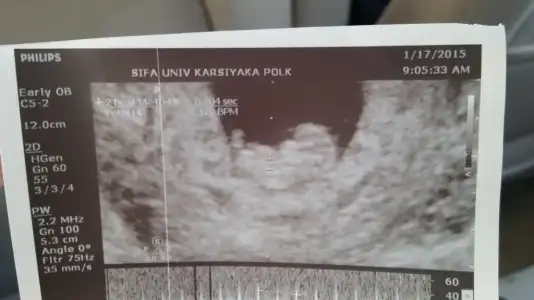

Prenses benceHanimlar arkadasimin bebesi 11 haftalik bi tahminde bulunurmusunuz

dr soylemeden siz gorun genital nub teorisi ( bebegin cinsiyeti)

bende senden bi yorum bekliyodum sagol canım doktoru erkeğe benzetmiş kesin olmamamakla birlikte bakalım sen kuz dıyosunPelo prenses

sence kesinmi prenses??Yaa be

bende senden bi yorum bekliyodum sagol canım doktoru erkeğe benzetmiş kesin olmamamakla birlikte bakalım sen kuz dıyosun

sence kesinmi prenses??

Tamam canım kesinleştiği zaman mutlaka yazarım...Allah razi olsun canm ins gönlündeki olur sen bizim kesinlerimize bakma yinede Dr değiliz yanildiklarimizda oluyor ama inş senin nazli kizin gelecek bence öğrenince haber et

Ceren kiz gibi ama yanilticida bi poz emin olamadim oyuzden[/QUOTE][QUOTE="Ceren2392, post: 39100222, mememinMerhaba :) 14 haftalığız ve cinsiyet belli değil dedi doktorum. Birde sîz bakarmısınız :)

Kız olmasi gerekiyor bence allah bilir tabiki ama bence kızKızlar benîm bebîşime de bi bakar mısınız ? 12+1 burada.

Ben çok anlamam ama sanki bana çıkıntı var erkek gibi geldi alttaki ultrason görüntüsünde.Kızlar bugün ki görüntüler Dr. hala belli olmaz diyor lütfen yorum yapın 12+4 günlük.Eki Görüntüle 1393076 Eki Görüntüle 1393078

Erkek xanim cikinti var gibiKızlar bugün ki görüntüler Dr. hala belli olmaz diyor lütfen yorum yapın 12+4 günlük.Eki Görüntüle 1393076 Eki Görüntüle 1393078

Cok buyuk ihtimal erkelkizlar yorum bekliyorum